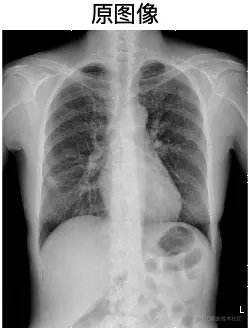

运行结果

image.png

subplot(2, 2, 1); imshow(I, []); title('原图像');

subplot(2, 2, 2); imshow(J, []); title('增强图像');

subplot(2, 2, 3); imshow(bw_temp, []); title('二值化图像');

subplot(2, 2, 4); imshow(I, []); hold on;